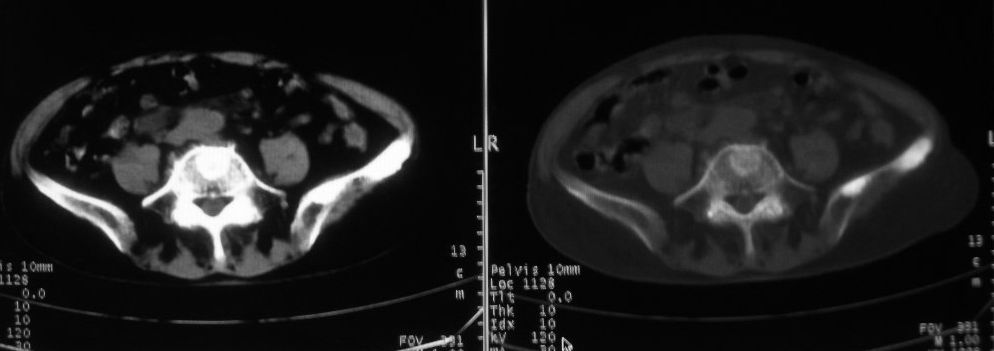

以下是引用zjzjr在2008-10-3 12:59:00的发言:[br]前列腺癌伴左髂骨\\腰椎转移可能性大.

以下是引用卜一在2008-10-3 13:40:00的发言:[br]前列腺癌!左髂骨\\腰椎转移?建议行全身骨扫描!

以下是引用深泽交通医院在2008-10-3 15:33:00的发言:[br]前列腺实性增大伴分叶状,与包膜间隙境界不清;椎体松质区间结节样密度影,考虑:前列腺癌,并椎体成骨性转移